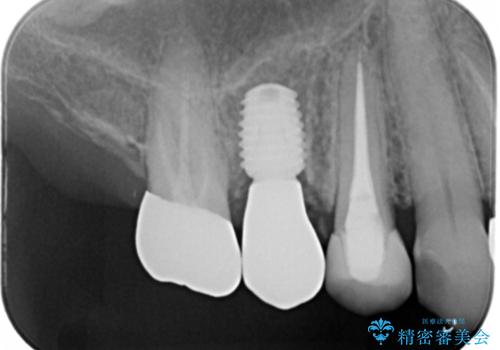

上の奥歯が折れた 抜歯即時埋入インプラント

- 右上小臼歯の破折を理由に来院された患者様です。

残根状態で保存不可能と判断し、抜歯した上で補綴することを提案しました。

インプラント治療を希望されたので治療の期間・回数の少ない抜歯即時埋入インプラントでの治療を計画しました。

抜歯と同時にインプラントを埋入することで治療の期間・回数を減らし、患者様への負担を大幅に軽減することができます。

今回の患者様においては、術後に痛みは発生せず良好な経過を得ることが出来ました。